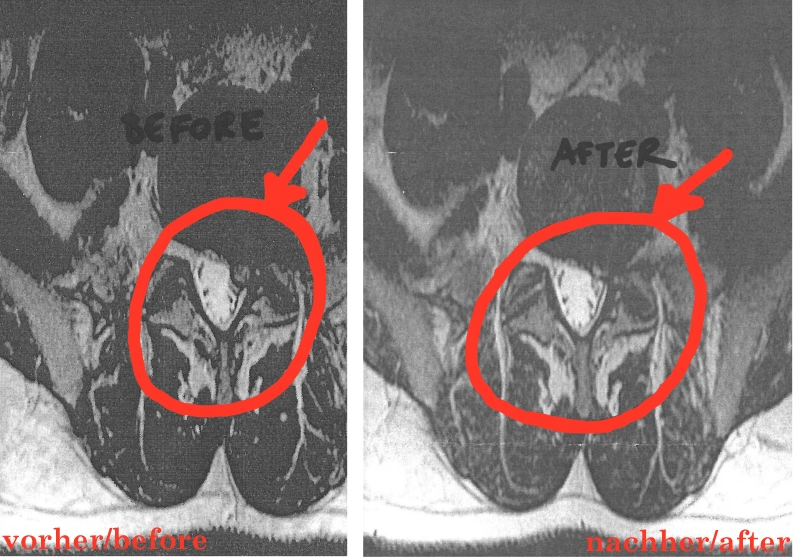

MRT einer Bandscheibe:

Die Veränderung erfolgte über die Behandlungszeit von acht Tagen.

Der Patient heisst David V. Er entschied sich gegen die „unumgängliche“ Operation und für Bios Logos.